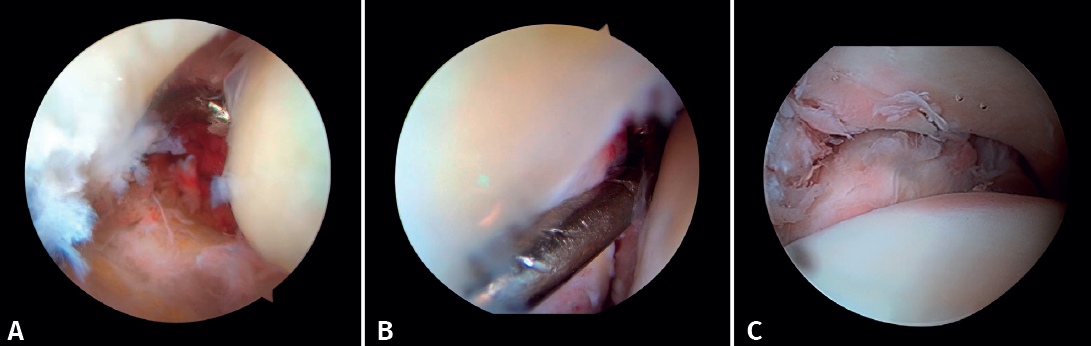

- Diagnosis of syndesmotic instability. Arthroscopy allows assessment of the integrity of the syndesmosis and the MCS on the radiograph and CT scan, especially in SER II and IV fractures. It has been shown that radiographic assessment is not always predictive of the syndesmotic lesion. In addition, arthroscopy ensures its anatomical reduction. Takao found that 87% (33/38) of the ankles with fractures had syndesmosis lesions detected by arthroscopy(20).

Arthroscopy allows both direct visualization and dynamic assessment of the syndesmosis(21,22).

- Being able to visualize the malleolar incisura together with radioscopic control allows us to ensure correct positioning of the incisura fibularis, especially in patients with unstable injuries where there is a risk of malreduction due to shortening or rotation of the fibula(5,24).

- Arthroscopy can help avoid overcorrection of the syndesmosis, which is highly arthrogenic(5,24)(Figure 6).

Xie showed that stabilization of the syndesmosis with a dynamic fixation system offers equivalent functional results and fewer complications compared to screw fixation(28). AAORIF allows the evaluation of joint congruency after anatomical reduction of both the posterior and anterior syndesmosis. It also allows assessment of the overcorrection that can result from over-compression of the tibiofibular mortise, which has been shown to be highly arthrogenic(29). During reduction of the syndesmosis, help is provided by a palpation probe which we should be able to insert once the syndesmosis has been fixed.